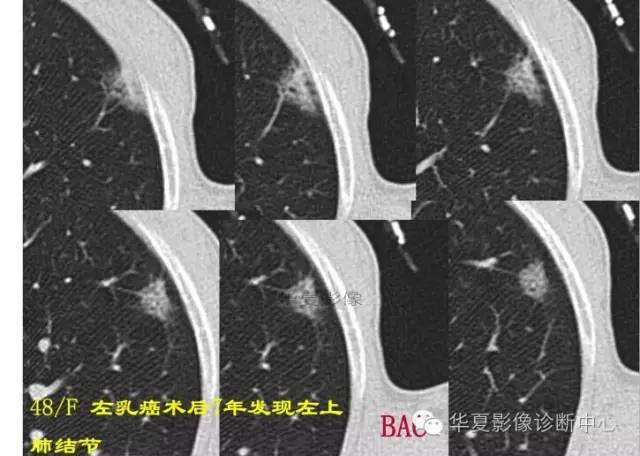

周围GGO边界清楚,分叶征、胸膜凹陷征、含气支气管,混合型GGO

磨玻璃结节良恶性影像分析策略 混合型,边界清楚、分叶征,考虑肺癌

边界清楚,分叶征,空泡征